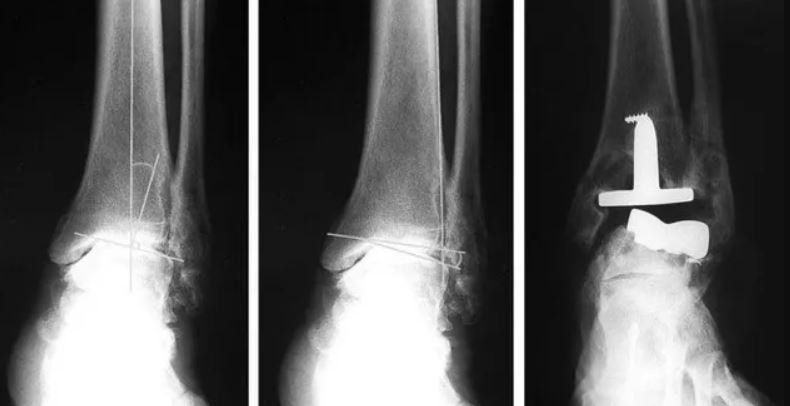

- revisione di protesi di caviglia;

- revisione di artrodesi.

La chirurgia di revisione è più complicata di quella eseguita in prima istanza, perché l’anatomia è stata modificata dal precedente intervento, perché molto spesso vi sono condizioni che rendono più difficile il lavoro del Chirurgo, quali la scarsa qualità dell’osso, la mancanza di un segmento osseo importante, la degenerazione della cartilagine, retrazioni cicatriziali e altre complicanze che hanno coinvolto i tessuti molli del Piede o della Caviglia.